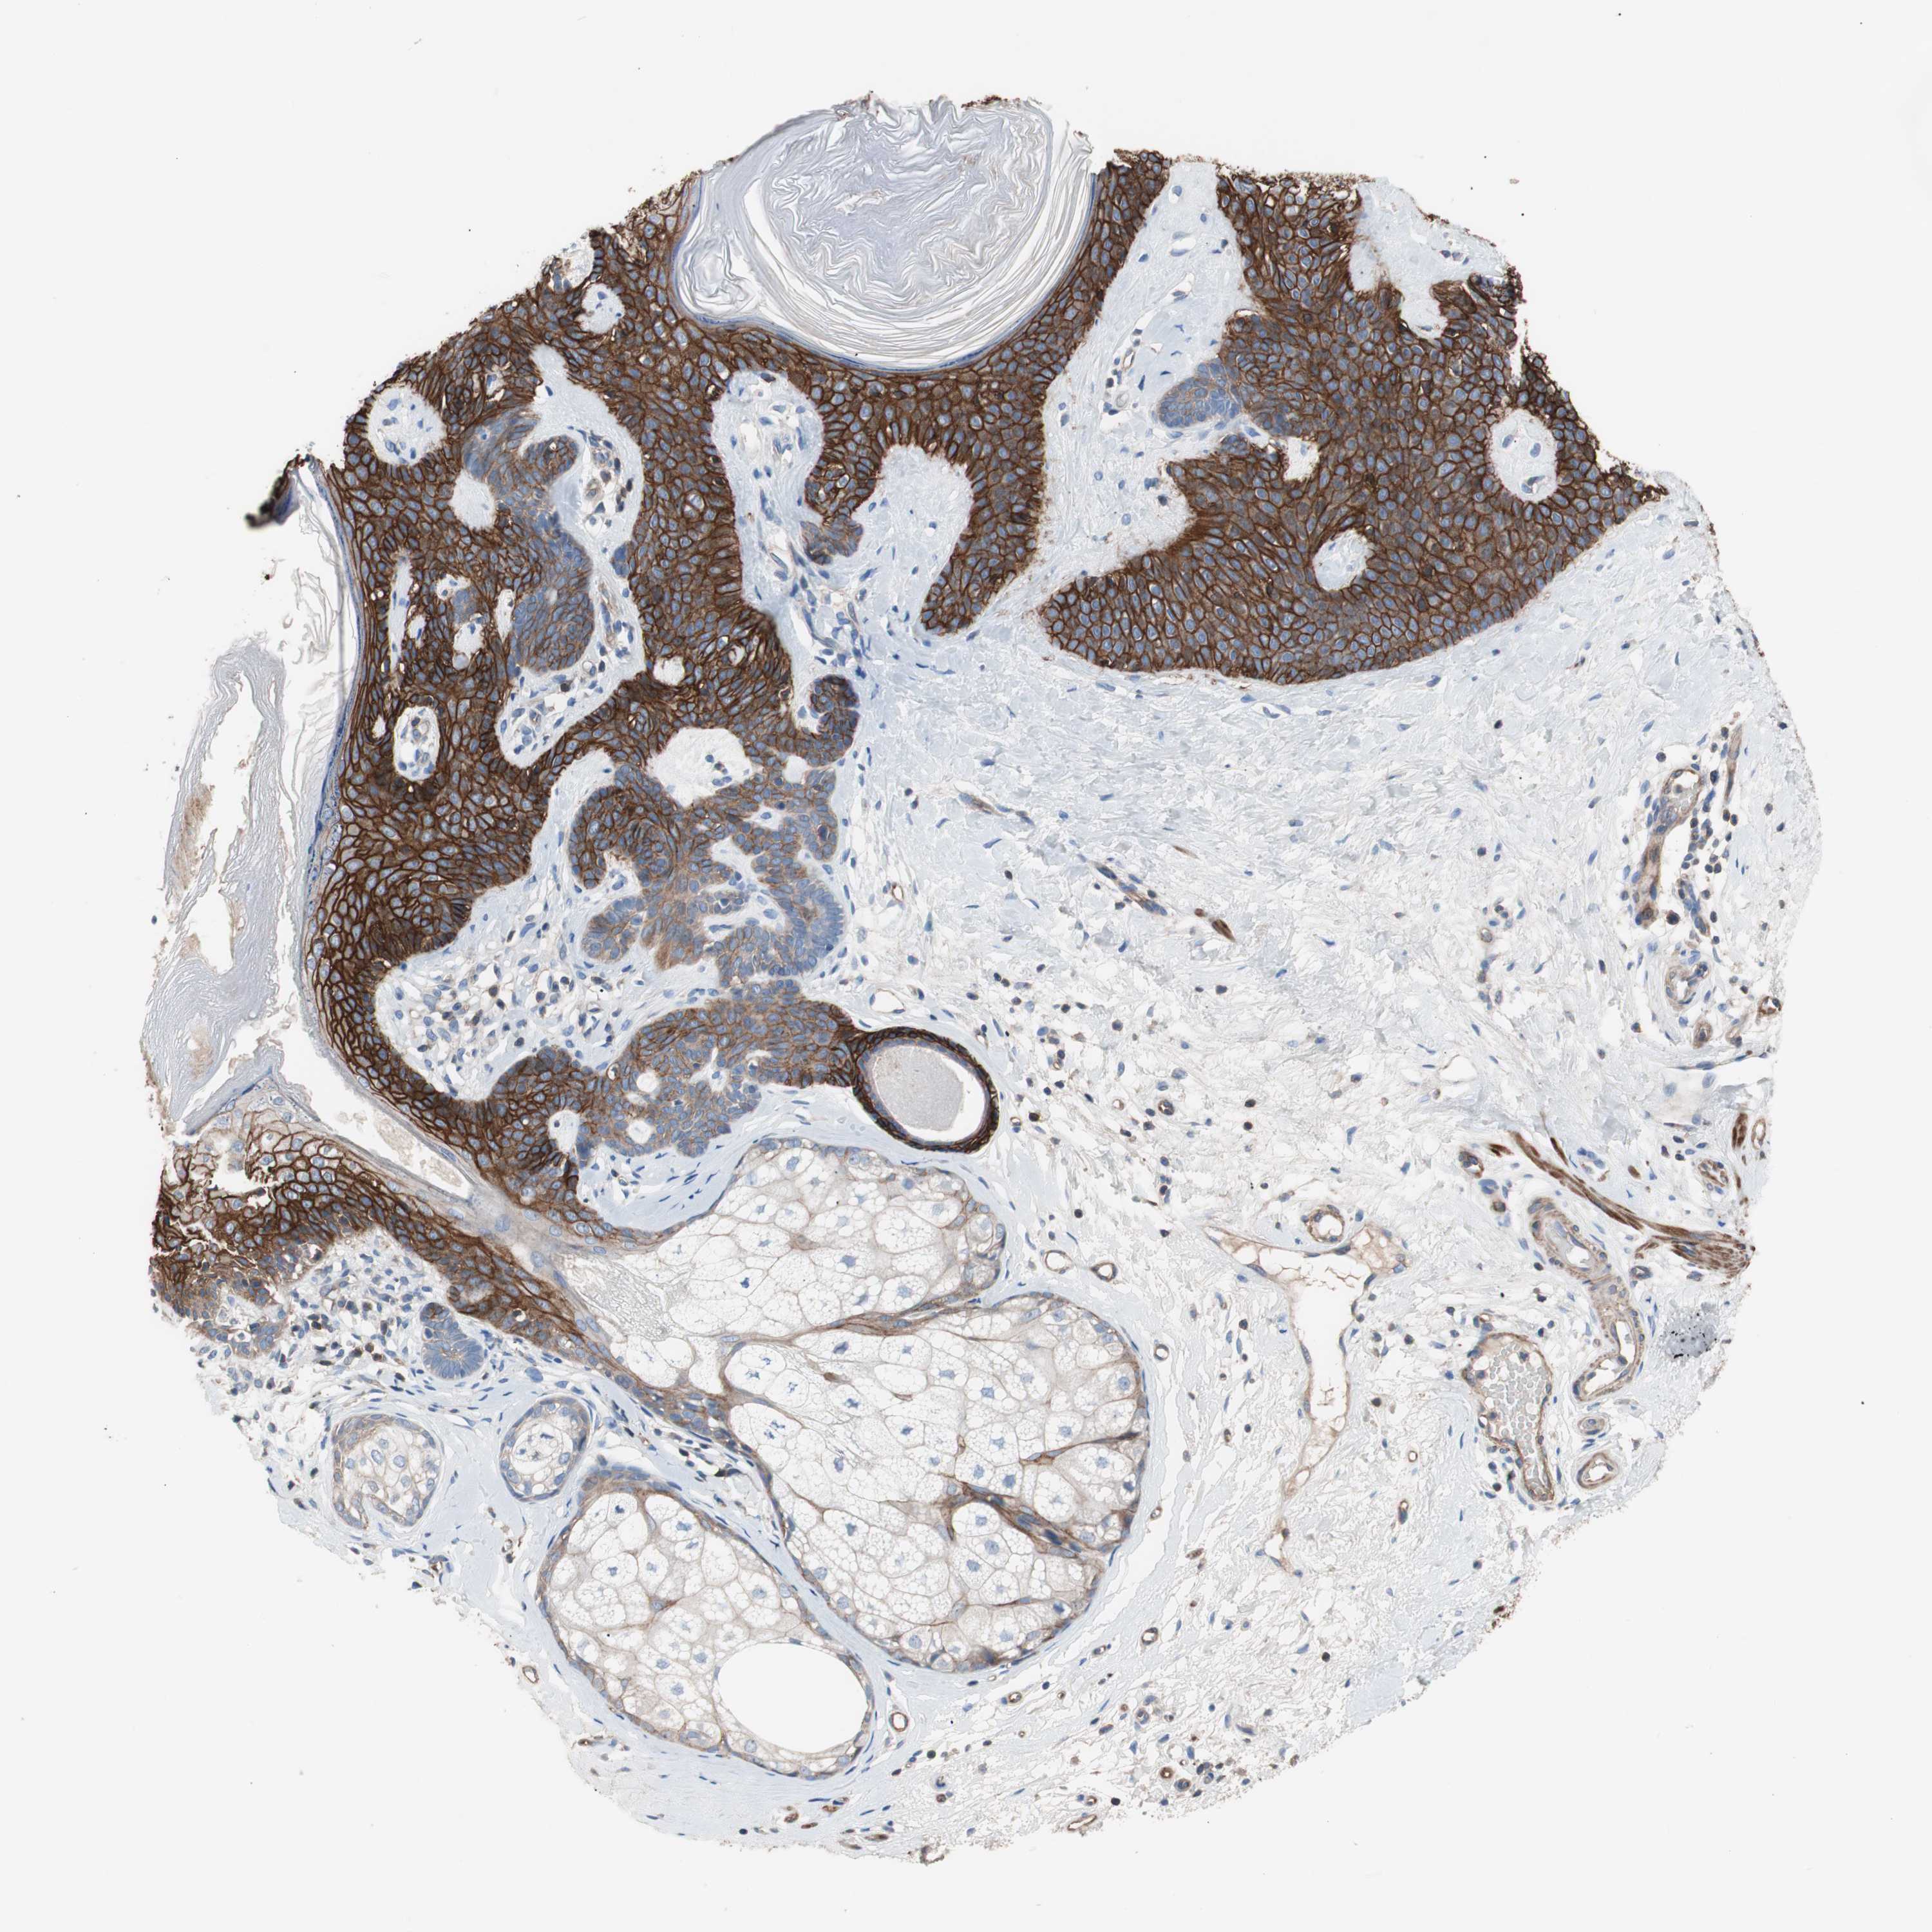

Antibody HPA006970

Staining

Medium

Intensity

Moderate

Quantity

75%-25%

Location

Cytoplasmic/membranous

Squamous cell carcinoma, NOS